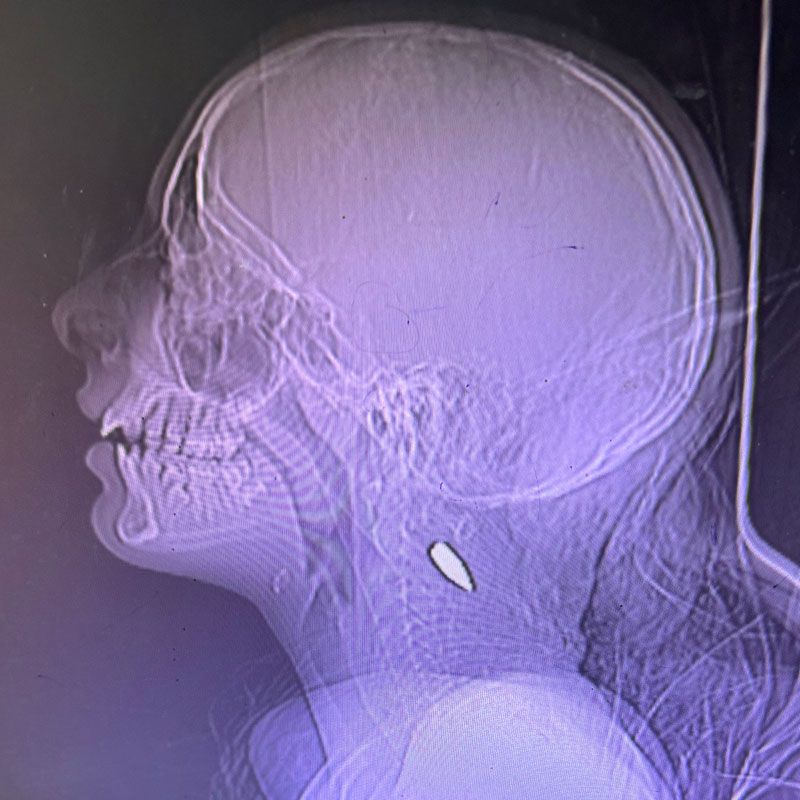

These photographs of X-rays were provided by Dr. Mimi Syed, who worked in Khan Younis from Aug. 8 to Sept. 5. She said: “I had multiple pediatric patients, mostly under the age of 12, who were shot in the head or the left side of the chest. Usually, these were single shots. The patients came in either dead or critical, and died shortly after arriving.” Dr. Mimi Syed

IB3.jpg

IB2.jpg

IB1.jpg